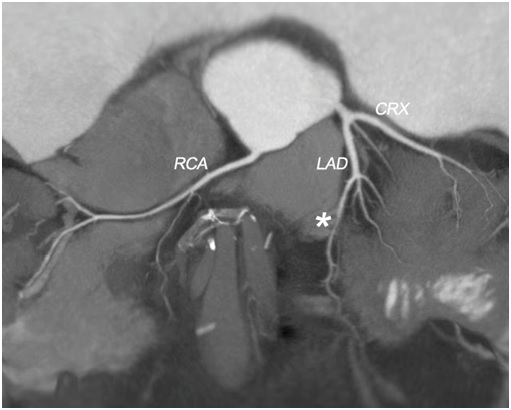

Figure 1: 2 D map of the coronary tree;

LAD: left descending coronary artery; RCA: right coronary artery; CRX: circumflex artery; star: indicates the myocardial bridge in the mid LAD.